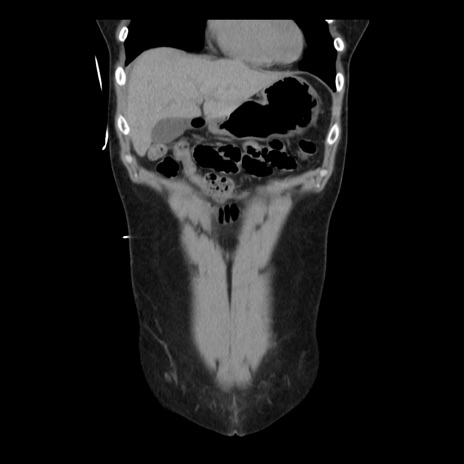

症例10(冠状断像)

【症例】 50歳代女性

【主訴】 腹痛

【現病歴】前日生レバーを食べた。今朝に排便あり。 昼前に突然発症の腹痛を生じ、当院救急外来を受診した。

【既往歴】 子宮筋腫にてで子宮全摘後

【身体所見】 意識清明、腹部:平坦、軟、下腹部やや左を中心に圧痛・反跳痛あり、筋性防御あり

【データ】WBC 7800、CRP 0.07